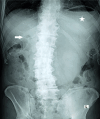

Gastric outlet obstruction in a patient